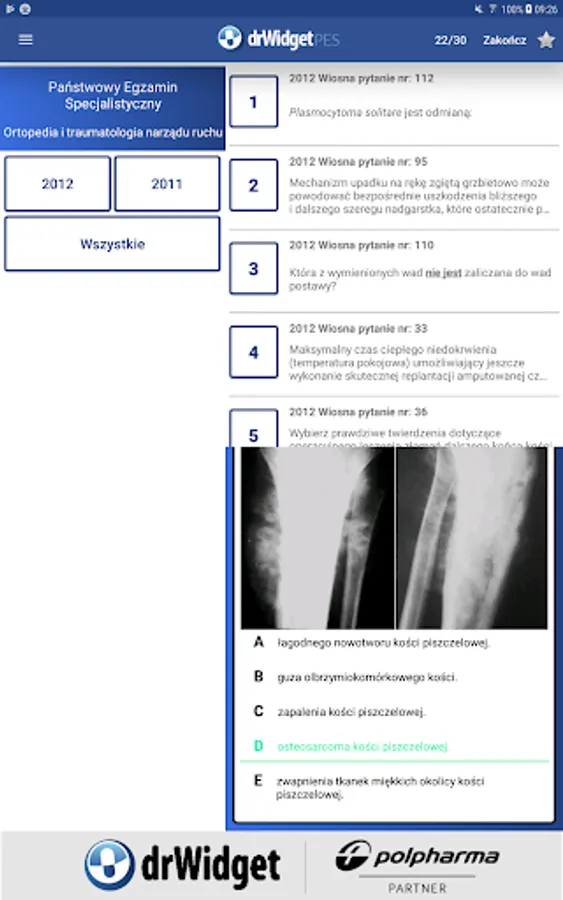

Database examination tests can be viewed in two ways: in the mode you have questions or exam.

In this mode, the system displays additional questions from the exam questions. When a user indicates a response, from the hand you receive information, whether it is correct. You can go through all the questions in sequence, you can also end the test on any question.

In test mode, the user decides how it wants to sit and choose what level of difficulty. The simplest option is to "question plus the correct answer." A more difficult variant requires the user to answer yourself. Its correctness can be checked on a regular basis or only when the result of the entire exam.

You can choose the display order of questions. This may be a random sequence, as well as the original, that is, one in which the question appeared on the exam. Moreover, the user can decide whether to pass the test, or divide it into parts.